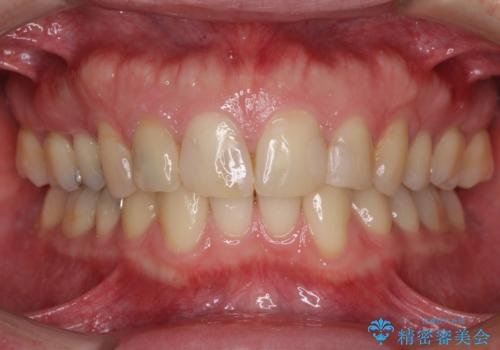

- 前歯の見た目を主訴にご来院された患者様です。虫歯治療を複数回繰り返して、前歯のつめものがつぎはぎになっていました。

患者様は前歯の見た目の改善を主訴にご来院されました。上の前歯6本とも古いつめものがつぎはぎになっていましたが、まずは1番目立つところを治すことをご希望でした。相談の結果、今回は2本できれいになるように工夫しました。